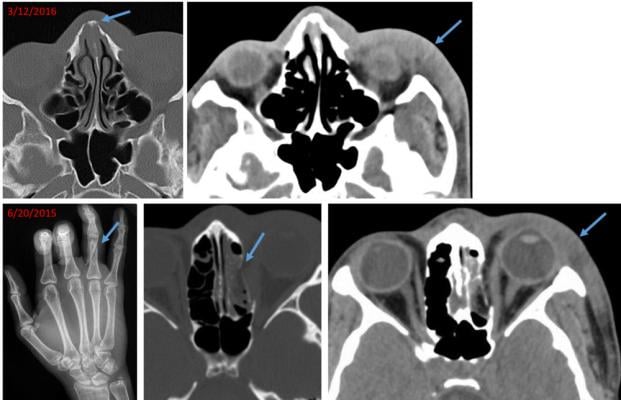

Image of 21-year-old woman, who presented with a chronic nasal bone fracture and soft tissue swelling of the left lateral face. Review of electronic medical records revealed presentation to an outside hospital 9 months ago with oblique fracture of the right ring finger proximal phalanx, blowout fracture of the medial wall of the left orbit and similar soft tissue swelling of the left face. Traumatic findings separated in time suggest recurrent violence. Image courtesy of Elizabeth George, M.D.

Medical images sometimes offer early clues that abuse is taking place. In fact, the case that inspired the study's principal investigator, Bharti Khurana, M.D., emergency radiology fellowship program director at Brigham and Women's Hospital., involved a young woman who arrived at the Emergency Department with an acute nasal bone fracture superimposed on an old, healed fracture. While going through prior medical images of the patient on the hospital's picture archiving and communication system (PACS), Khurana identified a recent wrist fracture. This pattern of recurrent injury made her voice her suspicion of intimate partner violence, a finding the referring physician initially had not suspected.

Along with providing information on presenting injuries, radiologists have access to a wealth of information through PACS that can show prior fractures linked to abuse. Old, healed fractures look distinct from acute fractures, Khurana said, and may be evident in the form of bone remodeling, deformity or focal bone thickening.

"In the emergency room setting, the priority is to identify acute pathologies," she said. "As a result, old fractures or fracture-related deformities may not be given sufficient importance. But the presence of old and acute fractures may be pivotal in making the diagnosis of intimate partner violence."